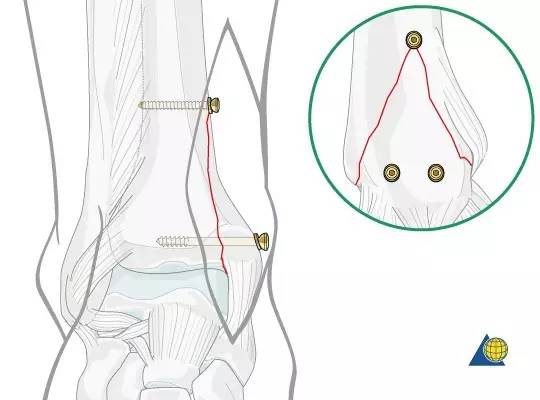

4 孔 1/3 管型钢板,骨折线远近端各两孔,近端采用皮质骨螺钉双皮质固定,注意第 2 枚螺钉应位于骨折线近端 3 mm 处。远端采用 4 mm 部分螺钉松质骨螺钉固定。